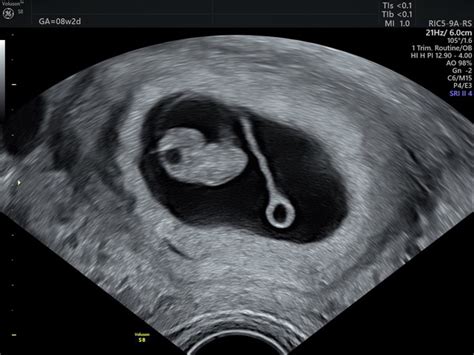

Merjenje dolžine materničnega vratu se običajno izvaja z vaginalnim ultrazvokom, ki je neboleča in varna metoda. Čeprav ni univerzalno sprejet standard, da bi se MV meril vsem nosečnicam rutinsko, se priporoča v določenih primerih ali na zahtevo nosečnice.

- Oblika MV: Poleg dolžine se pri ultrazvočnem pregledu lahko opazi tudi oblika MV. "Lijakasta" ali V-oblika lahko pomeni, da se MV začenja mehčati ali odpirati, čeprav je pomembno razlikovati med lijakastim segmentom maternične votline in dejanskim lijakastim MV.

- Lijakasta oblika MV: Če je MV dolg in zaprt 31 mm, ne more biti v obliki črke V, ampak kvečjemu Y. Navidezni lijak je pogosto spodnji segment maternične votline, ne pa odpiranje MV.